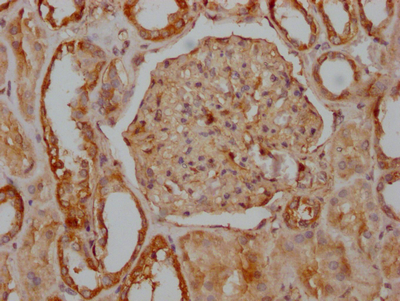

IHC image of CSB-RA548303A0HU diluted at 1:100 and staining in paraffin-embedded human kidney tissue performed on a Leica BondTM system. After dewaxing and hydration, antigen retrieval was mediated by high pressure in a citrate buffer (pH 6.0). Section was blocked with 10% normal goat serum 30min at RT. Then primary antibody (1% BSA) was incubated at 4℃ overnight. The primary is detected by a Goat anti-rabbit IgG polymer labeled by HRP and visualized using 0.05% DAB.